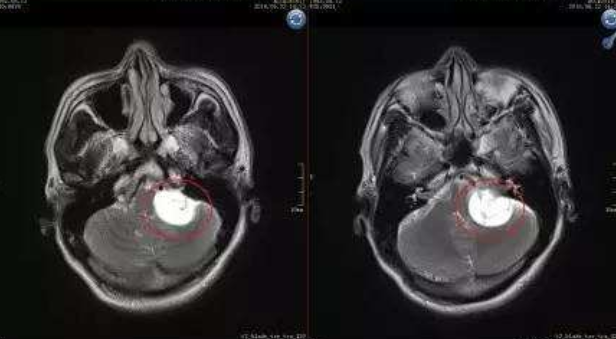

听神经瘤会癌变吗?听神经瘤是一种常见的良性脑瘤,也被称为前庭神经鞘瘤。这是由于听神经瘤是由连接内耳和大脑的主神经内膜发育而来,这被称为听觉或前庭耳蜗神经。它控制人的听力和平衡。在它旁边是控制面部运动的面神经。虽然听神经瘤是良性肿瘤,它们不会扩散到大脑。但良性肿瘤在生长过程中会压迫周围的组织,从而造成听力等各种问题,耳鸣就是听神经瘤的常见症状。如果肿瘤长得足够大,它还会影响附近的神经或大脑的重要功能。

当发展为大型听神经瘤时,肿瘤通常严重压迫脑干组织,手术风险较大,术后轻则面瘫、听力丧失,重则偏瘫、昏迷甚至死亡。手术是治疗大型听神经瘤合适且的办法。由于肿瘤体大,且与面听神经粘连较其紧密,术后发生面瘫及听力丧失的几率较大!全切肿瘤、术后没有面瘫、保留听力,这些对神经外科医生提出了较大的挑战!